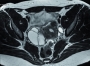

Le pelvis, qui abrite de multiples organes, reste bien mystérieux pour les jeunes patientes. En cas de douleurs, une exploration méthodique est nécessaire. Le Dr Léa Delbos* (gynécologue-obstétricienne, CHU d’Angers) rappelle la stratégie de prise en charge.

Egora : Quelle peut être l’origine de ces algies pelviennes ? Dr Léa Delbos* : Le pelvis renferme un grand nombre d’organes d’intérêt, utérus, ovaires et trompes certes, mais aussi la vessie et le rectum. Et tous sont susceptibles de provoquer des douleurs pelviennes. L’imagerie, l’échographie par voie abdominale sus-pubienne, permet d’écarter des malformations utérines rares comme un utérus cloisonné ou bicorne, des malformations rénales. En cas de douleurs chez une jeune fille réglée, si l’histoire familiale le justifie (une apparentée au premier degré), l’endométriose doit être recherchée, en particulier si ces douleurs sont rythmées par les règles, ce qui reste souvent le cas au début de la maladie. Si elles ne le sont pas, on doit y penser, mais pas plus qu’à d’autres étiologies… Un syndrome des ovaires polykystiques ? Les douleurs - pelviennes en général - , sont en lien avec l’ovulation, peuvent l’être aussi avec les règles. Le spectre symptomatique est à l’évidence plus diffus. Enfin, à l’instauration des règles, la jeune fille peut souffrir d’une dysménorrhée primaire, avec des règles abondantes dont le flux se normalise au fil des cycles. Parfois il existe des douleurs à la mobilisation utérine et pelviennes associées, secondaires à un rapport sexuel non protégé. Cette situation oblige à un prélèvement de l’endocol et du vagin pour visualiser directement les germes d’une infection sexuellement transmissible, chlamydiæ et gonocoques essentiellement, parfois E. coli ou Proteus mirabilis venus du colon proche. Les douleurs d’infections urinaires sont plus volontiers à type de brûlures de l’urètre à la miction, pollakiurie, petite fièvre, et éventuellement hématurie. Le diagnostic, au-delà de l’interrogatoire, est porté sur la présence de leucocytes au test de la bandelette urinaire. Quand cystites récidivantes il y a, elles accompagnent fréquemment les premiers rapports sexuels, parfois jusqu’au premier enfant. Des signes plus volontiers digestifs sont en faveur d’une pathologie chronique intestinale : un Crohn susceptible de débuter à l’adolescence ou plus rarement une rectocolite hémorragique. Un syndrome du côlon irritable est une éventualité également, associant ballonnements, troubles du transit et douleurs pelviennes. Un ECBU et une échographie pelvienne, voire une prélèvement bactériologique gynécologique, permettent de faire l’essentiel des diagnostics d’algies pelviennes.   Quelles prises en charge peut-on proposer ? Avant que n’apparaissent les règles, y compris en cas d’endométriose familiale, les contraceptifs ou les anti-inflammatoires non stéroïdiens ne sont pas indiqués sur des algies pelviennes. En cas d’ovaires polykystiques, on propose un traitement à base de contraceptifs, estroprogestatif ou microprogestatif en continu sous la forme d’implant, de dispositif intra-utérin (pour les adolescentes non vierges) ou de pilule (type désogestrel). Cette contraception estroprogestative est de 2è génération en première intention. Un protocole calqué sur ce modèle est proposé en cas de dysménorrhées primaires pour une mise au repos des ovaires si les algies ne cèdent pas avec un antalgique type paracétamol ou un antispasmodique. En cas d’infection génitale à chlamydiæ identifiée ou simplement suspectée (sur une infection du partenaire), mieux vaut traiter (voire surtraiter) en raison du très grand risque d’infertilité ultérieure liée à une infection qui se développerait à bas bruit, la bactérie ayant une particulière affinité pour les trompes : 4 comprimés d’azithromycine 250 mg en une prise en cas d’exposition ; de la doxycycline 100 mg matin et soir pour 7 jours quand l’infection est avérée. Une prescription qui teint compte aussi des allergies de la patiente. Un épisode de cystite doit être traité par antibiotique (de la fosfomycine trométamol) en une prise pour les femmes ; au-delà de 4, quand la cystite est considérée comme à répétition, en raison d’une colonisation probable de l’arbre urinaire, chaque infection doit être documentée par un ECBU pour une antibiothérapie adaptée.